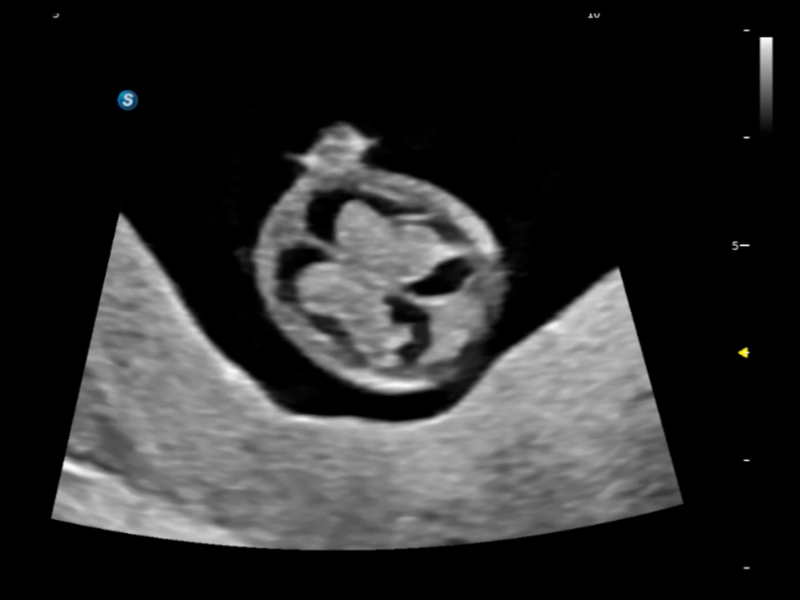

作为开立医疗全新打造的超高端旗舰超声产品,从探头抬起唤醒开启扫查到多维探头发射接收,通过先进的场成像发射、自适应聚合重建等技术,基于RF Data原始射频数据在图像生成、高端功能等方面实现突破,提供多科室综合临床解决方案。

独有场成像发射技术

自适应聚合重建技术